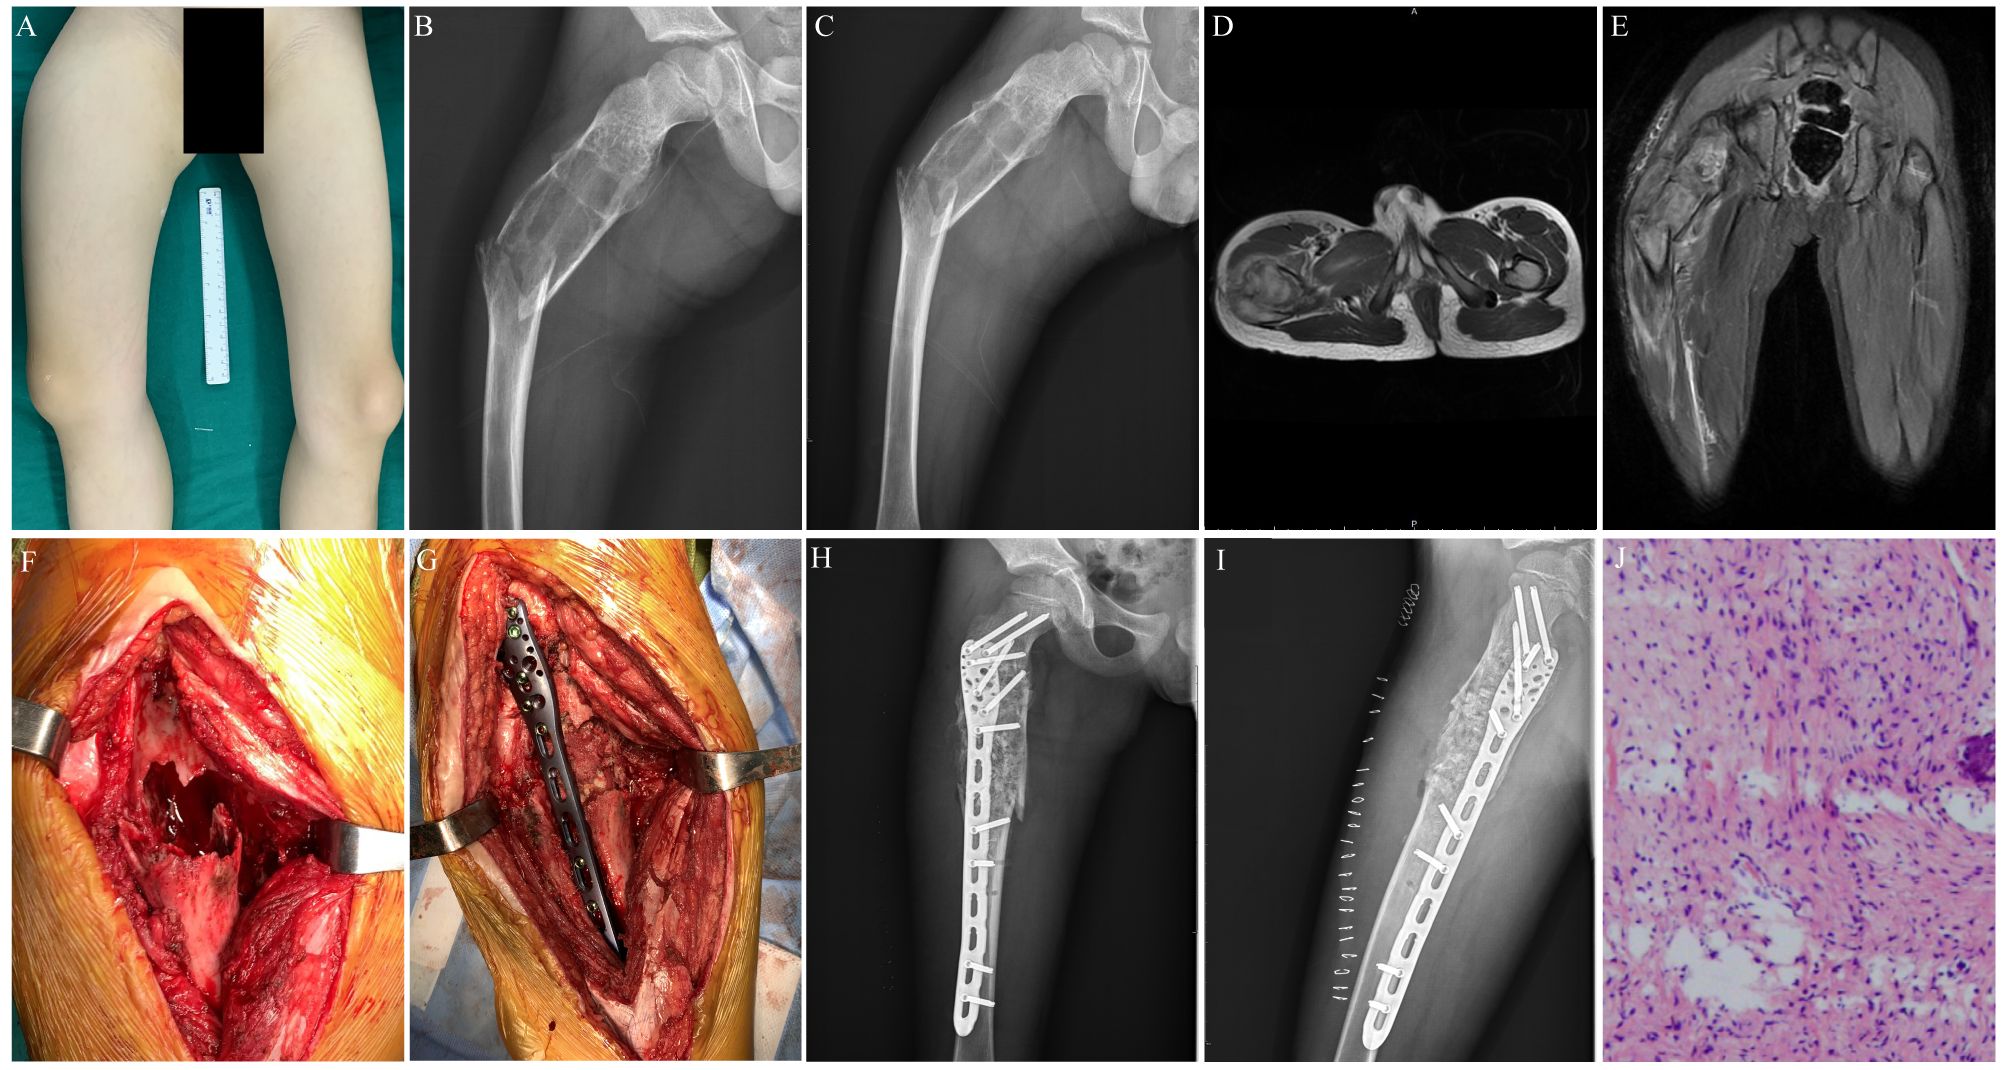

Figure 2. Preoperative, postoperative, and operative images of a 7-year-old male patient with a pathological fracture of the proximal end of the right femur. (A) A general image of the patient before surgery. (B) Preoperative lateral x-ray image of the patient. (C) Preoperative posteroanterior x-ray image of the patient. (D) Preoperative transverse MR image of the patient. (E) Preoperative coronal MR image of the patient. (F) Enlarged cortical window with adequate scraping of the lesion. (G) Bone grafting, internal fixation with a suitable adult 3.5 mm proximal humerus locking plate, and gross fracture reduction. (H) Postoperative x-ray image of the patient. (I) Postoperative lateral x-ray image of the patient. (J) Postoperative histopathological diagnosis of the patient.